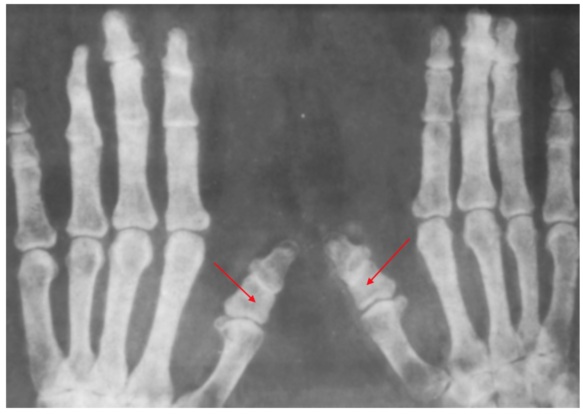

| Тип D | Недоразвитая дистальная фаланга приводит к укорочению больших пальцев на руках и ногах. На медицинском языке такое явление называют брахимегалодактилия. |

Врачи чаще диагностируют у пациентов брахидактилию большого пальца типа A и D. Самой тяжелой формой патологии является тип B, а E – редко встречается.